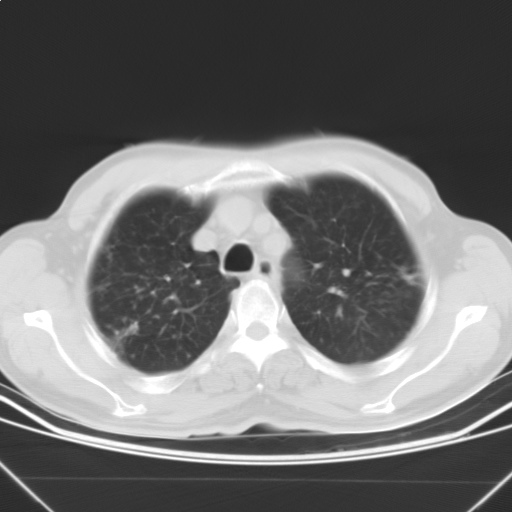

以下是引用随光逐影在2009-5-1 13:53:00的发言:[br]考虑为:1)两肺血行播散型肺结核;2)右肺下叶炎症感染。3)右侧胸膜增厚。